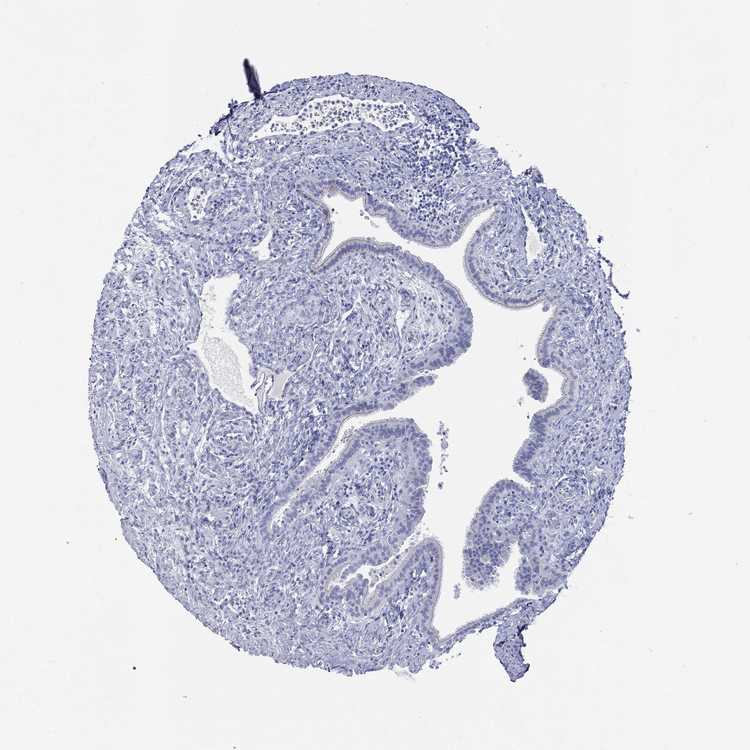

TISSUE PRIMARY DATA FALLOPIAN TUBE Show tissue menu

FALLOPIAN TUBE - Antibody stainingi

Antibody staining in the annotated cell types in the current human tissue is reported as not detected, low, medium, or high, based on conventional immunohistochemistry profiling in selected tissues. This score is based on the combination of the staining intensity and fraction of stained cells.

Each image is clickable and will lead to virtual microscopy that enables deeper exploration of all samples and also displays staining intensity scores, fraction scores and subcellular localization as well as patient and tissue information for each sample.

Antibody HPA070355Antibody HPA078303

Glandular cells Not detectedNot detected